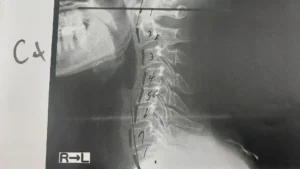

重度の眼精疲労についても上部頚椎の神経圧迫が関係している可能性が考えられ、頚椎1番と2番を正しい位置へ調整した際には「目がパッと開いた感じがする」とおっしゃっていました。